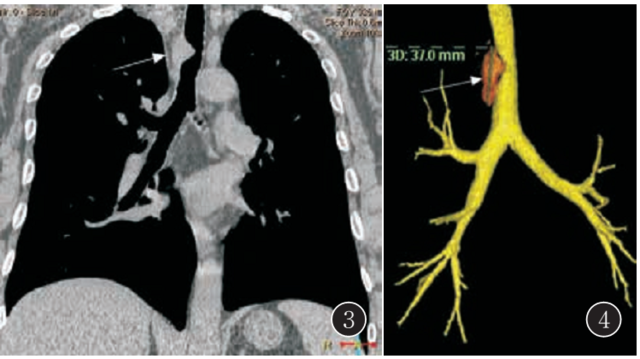

气管Rosa-iDorfman病

气管Rosa-iDorfman病气管Rosa-iDorfman病气管Rosa-iDorfman病气管Rosa-iDorfman病气管Rosa-iDorfman病气管Rosa-iDorfman病气管Rosa-iDorfman病